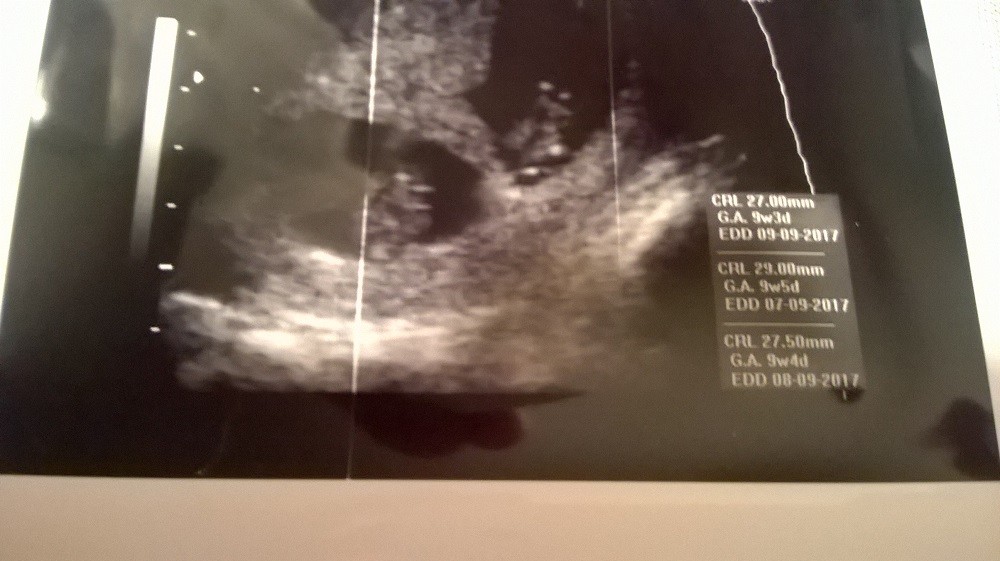

Moje dzidki zdrowe ...:)

WP_20170207_014.jpg

• WP_20170207_014.jpg

163,2 KB · Wyświetleń: 675